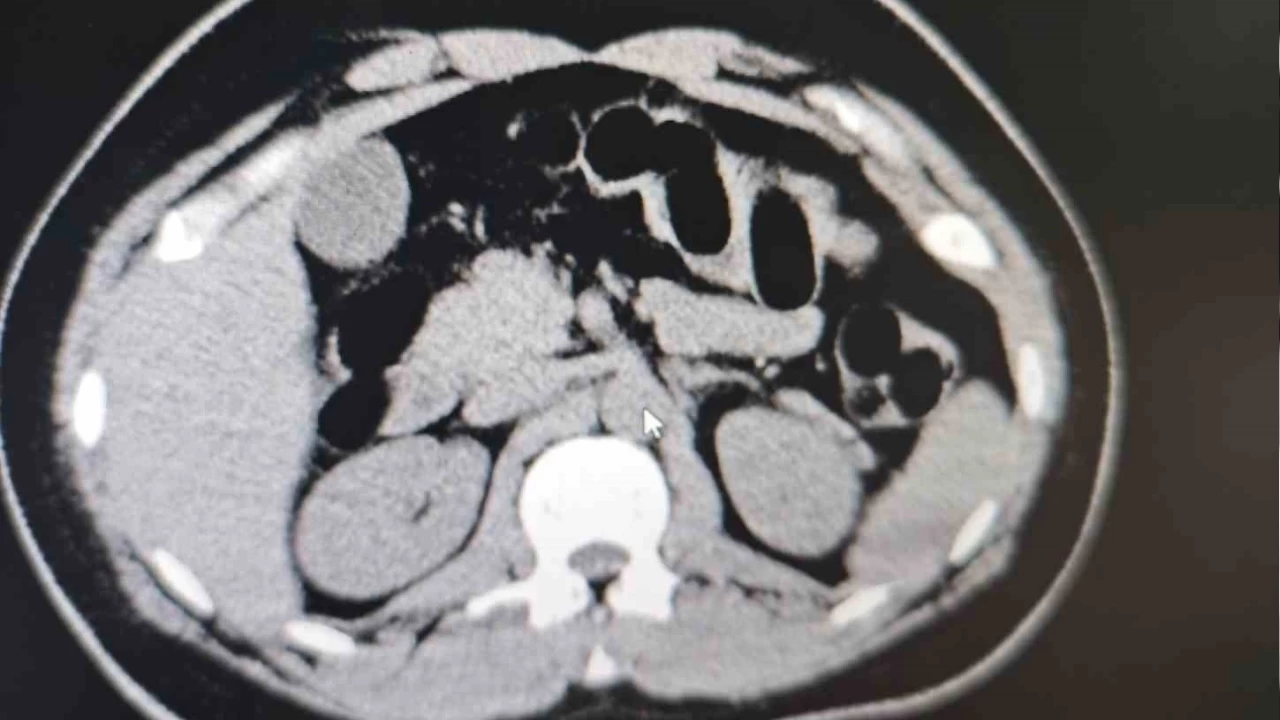

Otobüste yolcu olarak bulunan S.S. isimli şahıs, görevlilerimizin sorgulaması sonucunda şüpheli görülerek hastaneye sevk edilmiştir. Hastanede yapılan iç beden muayenesi ve tomografi görüntüleri sonucunda, şahsın midesinde uyuşturucu madde taşıdığı tespit edilmiştir.

Hastanede yapılan tespit sonrasında şüpheli şahsın midesinden toplam 84 adet kapsül içerisinde daralı ağırlıkları 842 gr gelen eroin maddesi ele geçirilmiştir. Şüpheli şahıs, 'Uyuşturucu ve Uyarıcı Madde Ticareti' suçundan gözaltına alınmış, işlemlerinin ardından adli makamlara sevk edilmiş ve tutuklanmıştır. Uyuşturucu ile mücadelemiz kararlılıkla devam etmektedir' denildi.